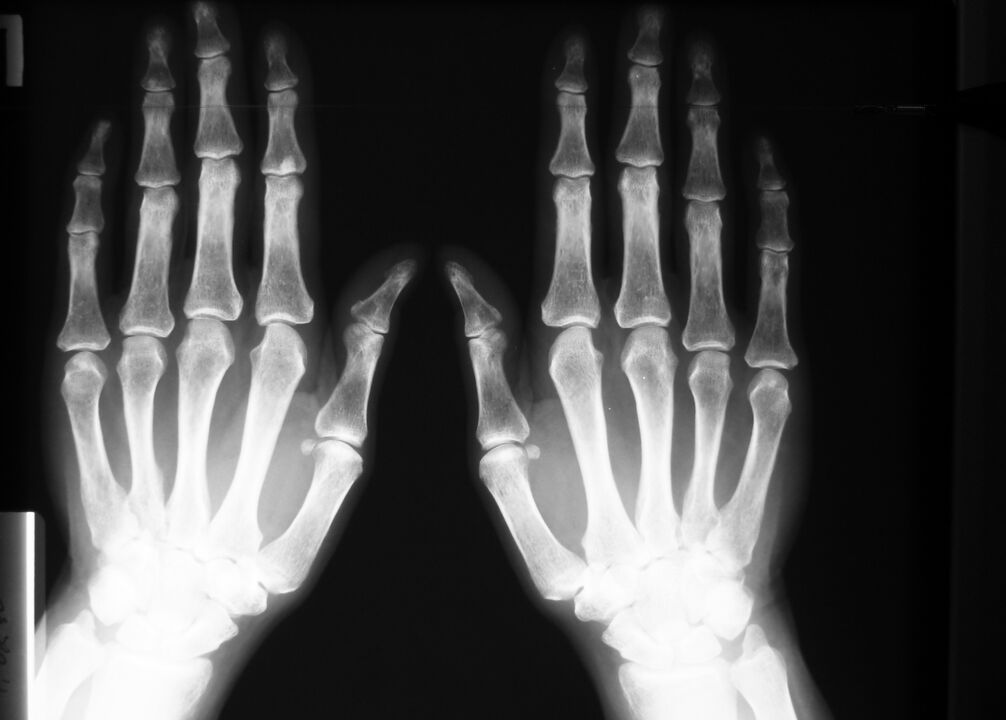

In caso di malattie degenerative e lesioni – alterazioni delle articolazioni: tessuto osseo e cartilagineo, visibili tramite radiografie o risultati della tomografia computerizzata.

La risonanza magnetica fornirà anche un quadro completo dei cambiamenti nei tessuti molli in caso di infiammazione del tendine, in caso di rottura di un legamento o di un muscolo.